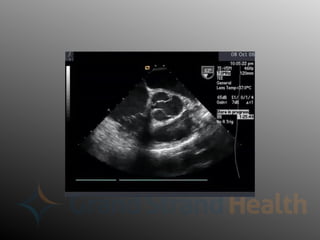

Diagnosis - Echocardiography

• Transthoracic Echo

– Widely variable

sensitivity/specificity

– Blind spot behind trachea and left

mainstem bronchus

• Transesophageal Echo

– Sensitivity as high as 98%

– May give useful surgical anatomical

information

– Often done in peri-operative period

Diagnosis - Echocardiography •Transthoracic Echo – Widely variable sensitivity/specificity – Blind spot behind trachea and left mainstem bronchus • Transesophageal Echo – Sensitivity as high as 98% – May give useful surgical anatomical information – Often done in peri-operative period

• #19 Sensitivity drops off when imaging the proximal aorta, TTE is better in this case

• #21 TEE of proximal dissection